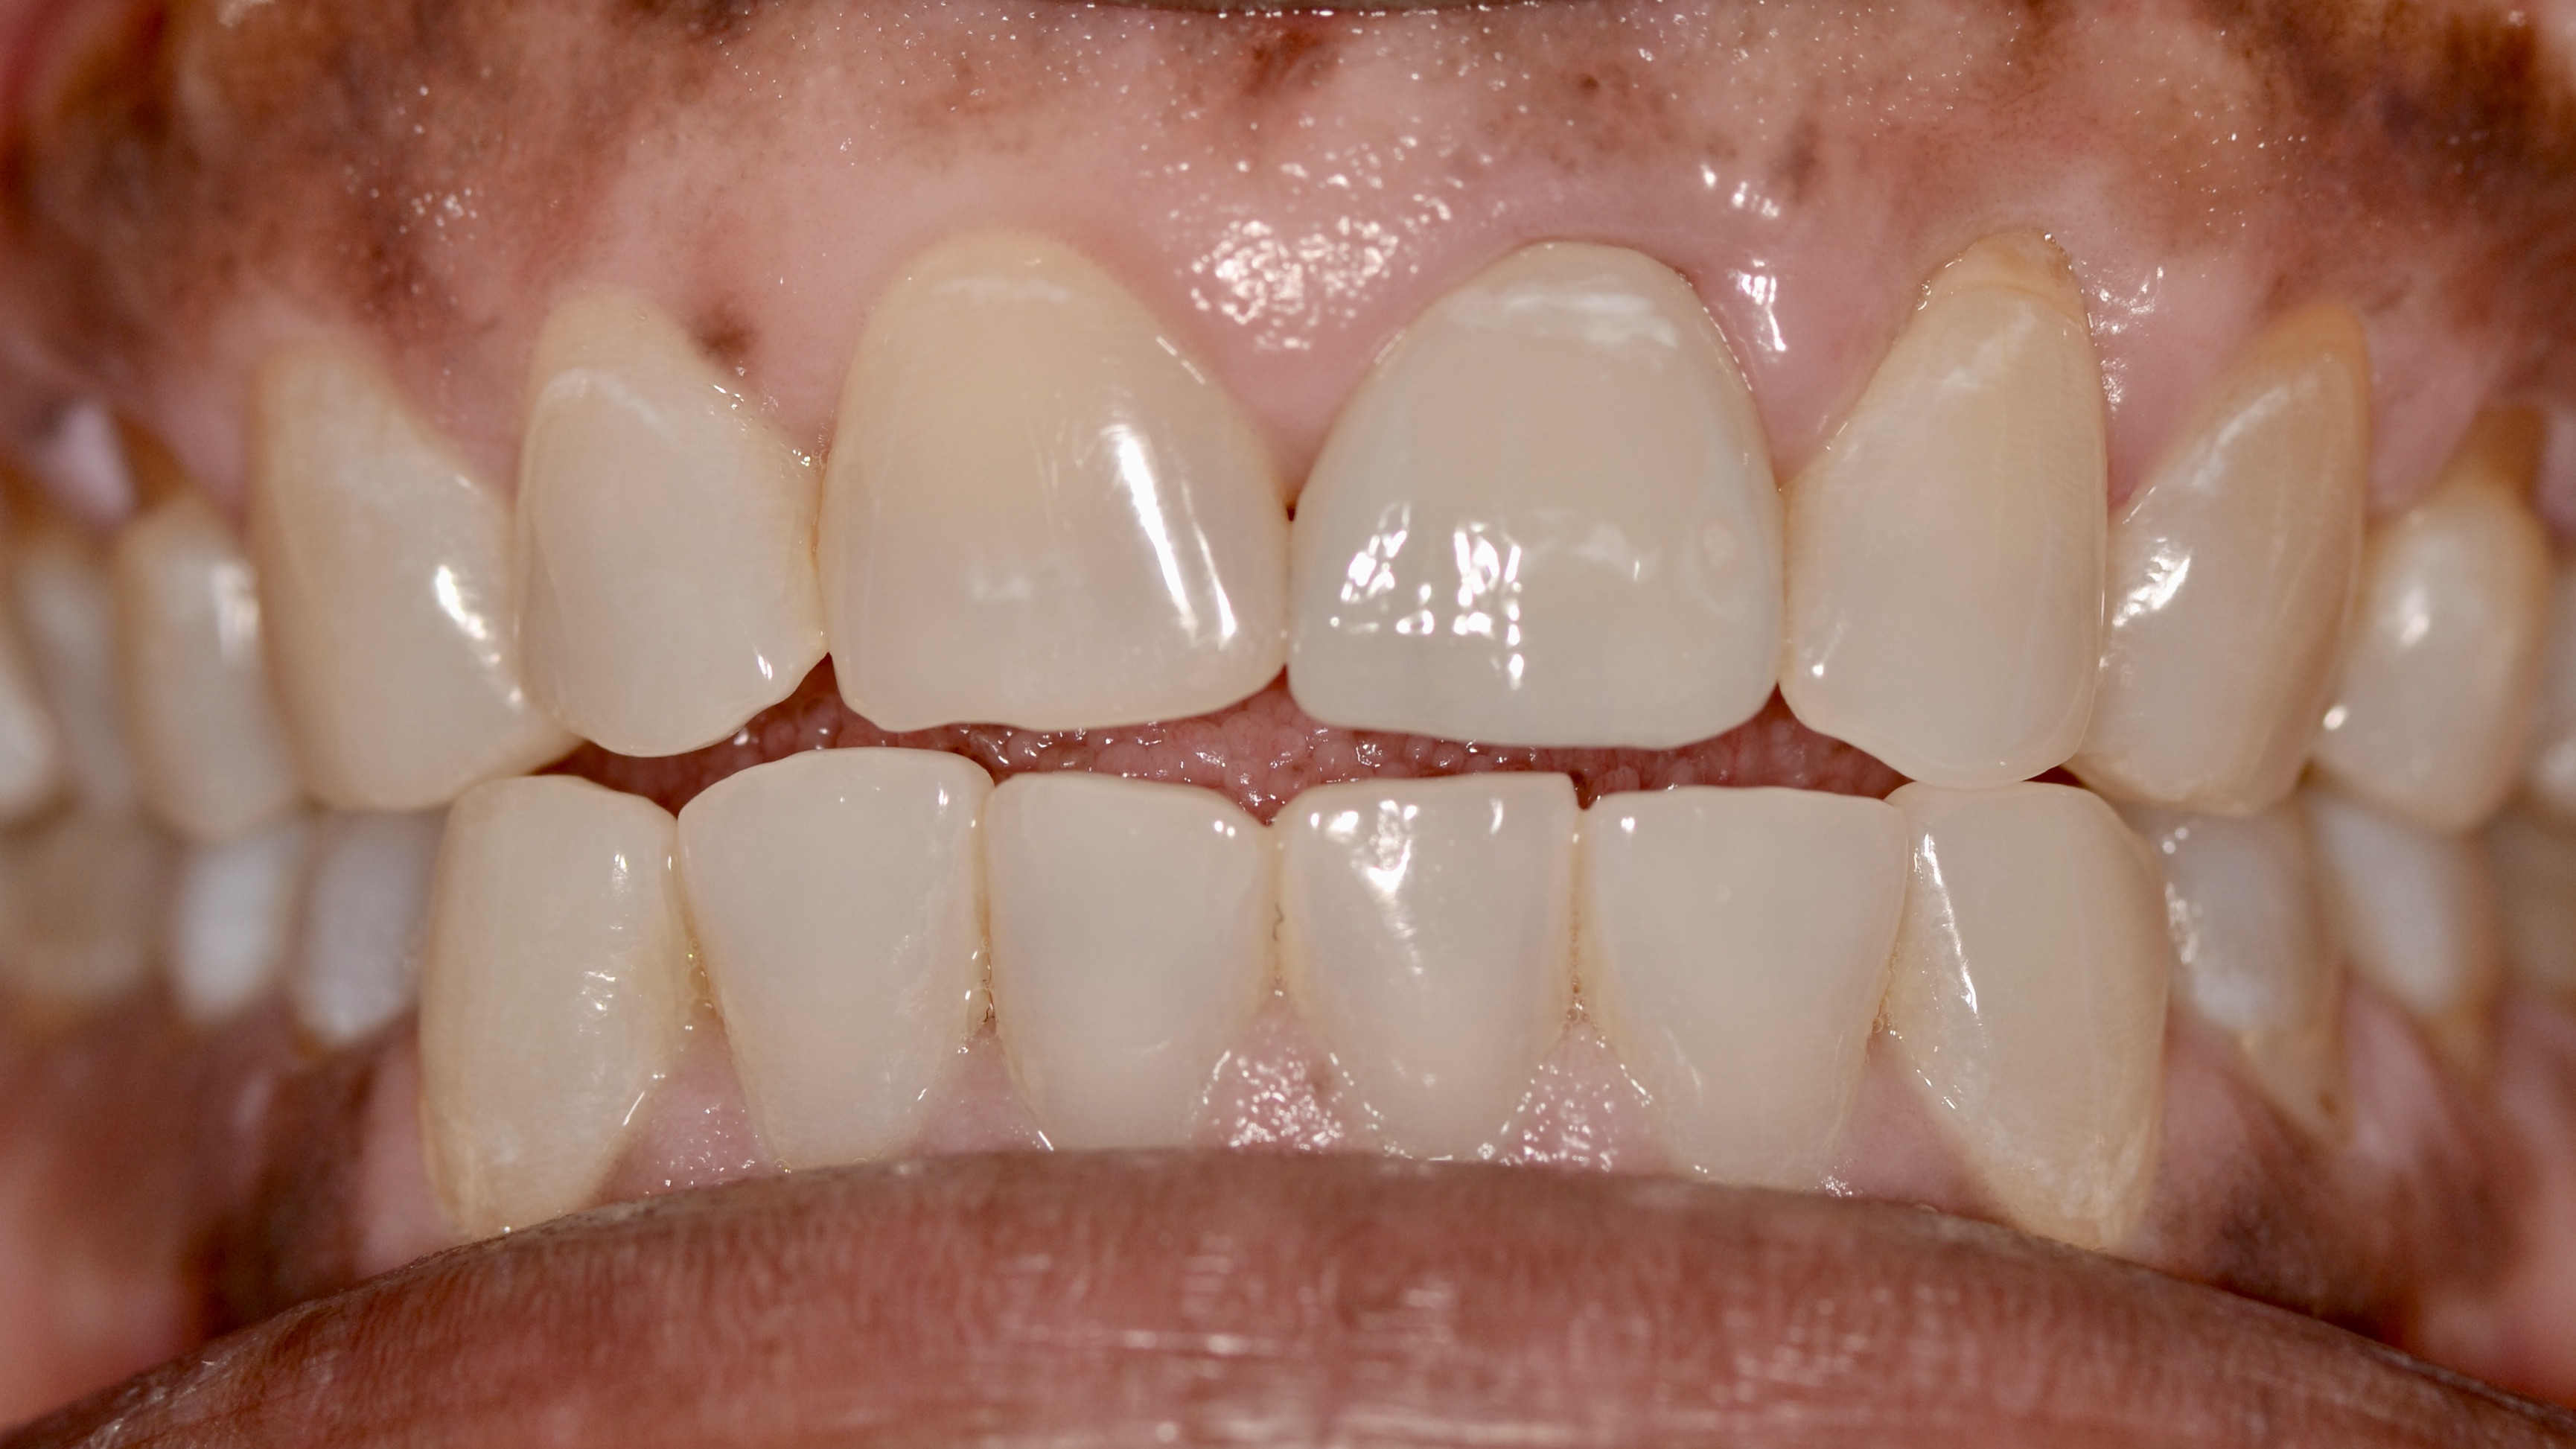

Front Tooth Trauma